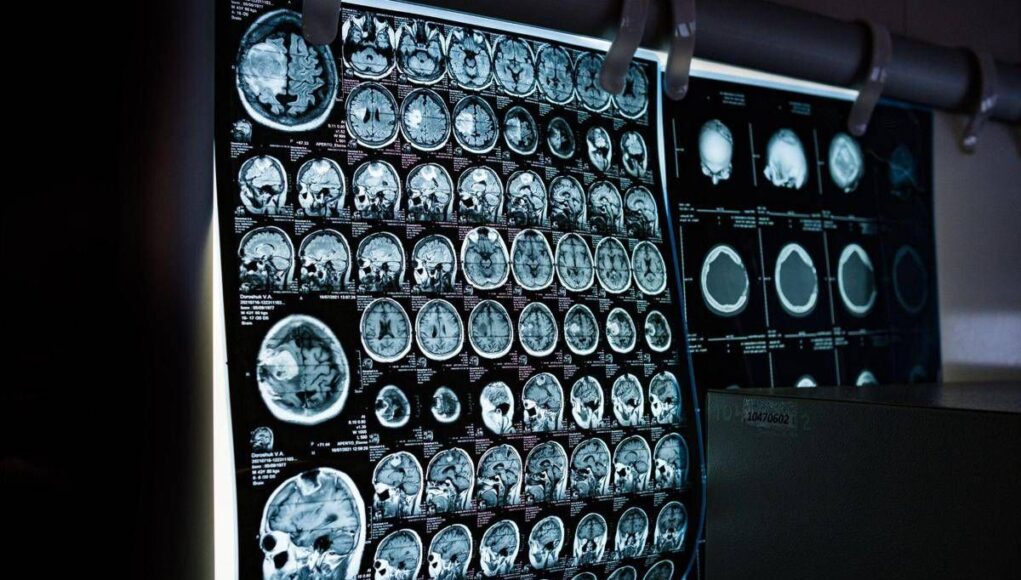

Uno spray nasale testato sui modelli animali potrebbe invertire l’invecchiamento del cervello con sole 2 dosi, riducendo drasticamente l’infiammazione cerebrale, ripristinando le centrali energetiche cellulari del cervello e migliorando così significativamente la memoria. Un processo di ringiovanimento che agirebbe nel giro di poche settimane per durare mesi.Â

E’ il risultato dello studio condotto dai ricercatori della Texas A&M University (Naresh K. Vashisht College of Medicine) negli Stati Uniti. Lo spray contiene minuscole particelle biologiche note come vescicole extracellulari (Ev), che agiscono come veicoli di consegna con a bordo un potente carico genetico, i microRna. Le sostanze aggirano lo scudo protettivo del cervello e viaggiano direttamente nel tessuto cerebrale, dove vengono assorbite. Arrivati a destinazione nelle cellule immunitarie residenti nel cervello, i microRna ‘spengono’ i sistemi noti per essere responsabili dell’infiammazione cronica nel cervello che invecchia.Â

Per spiegare il senso di questo processo, gli scienziati invitano a immaginare il cervello come un motore ad alte prestazioni: nel corso dei decenni questo motore non solo si usura, ma inizia anche a surriscaldarsi. Piccoli ‘focolai’ di infiammazione covano nelle profonditĂ del centro della memoria, creando una persistente nebbia mentale (brain fog) che rende piĂą difficile pensare, formare nuovi ricordi o persino adattarsi a nuovi ambienti, aumentando al contempo il rischio di disturbi come il morbo di Alzheimer. Questo processo a lenta combustione viene chiamato neuroinfiammazione. E per decenni si è pensato che fosse il prezzo inevitabile dell’invecchiamento. Ma il nuovo studio, pubblicato sul ‘Journal of Extracellular Vesicles’, suggerisce che l’ondata infiammatoria potrebbe essere reversibile.Â

Il team guidato da Ashok Shetty, distinguished professor dell’ateneo e associate director dell’Istituto di medicina rigenerativa, insieme ai ricercatori senior Madhu Leelavathi Narayana e Maheedhar Kodali, ha sviluppato lo spray nasale e ha verificato che a livello cellulare il trattamento ha ricaricato i mitocondri neuronali, ovvero le centrali energetiche che si trovano all’interno delle cellule cerebrali. La terapia ha dissipato la nebbia mentale e ha anche migliorato fisicamente la capacitĂ del cervello di elaborare e immagazzinare informazioni.Â